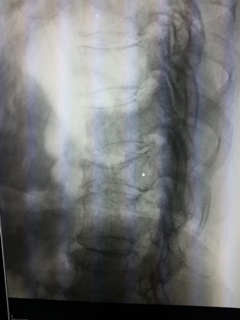

ภาพรังสีแสดงการยุบของกระดูกสันหลังหลายระดับ วิธีการดู คือ จะสังเกตจากความสูงของกระดูกสันหลังเทียบกันในแต่ละระดับ จะพบว่าส่วนของกระดูกสันหลังที่ยุบลงนั้นจะมีความสูง

ของกระดูกสันหลังลดลงเมื่อเทียบกับกระดูกสันหลังที่อยู่ติดกัน